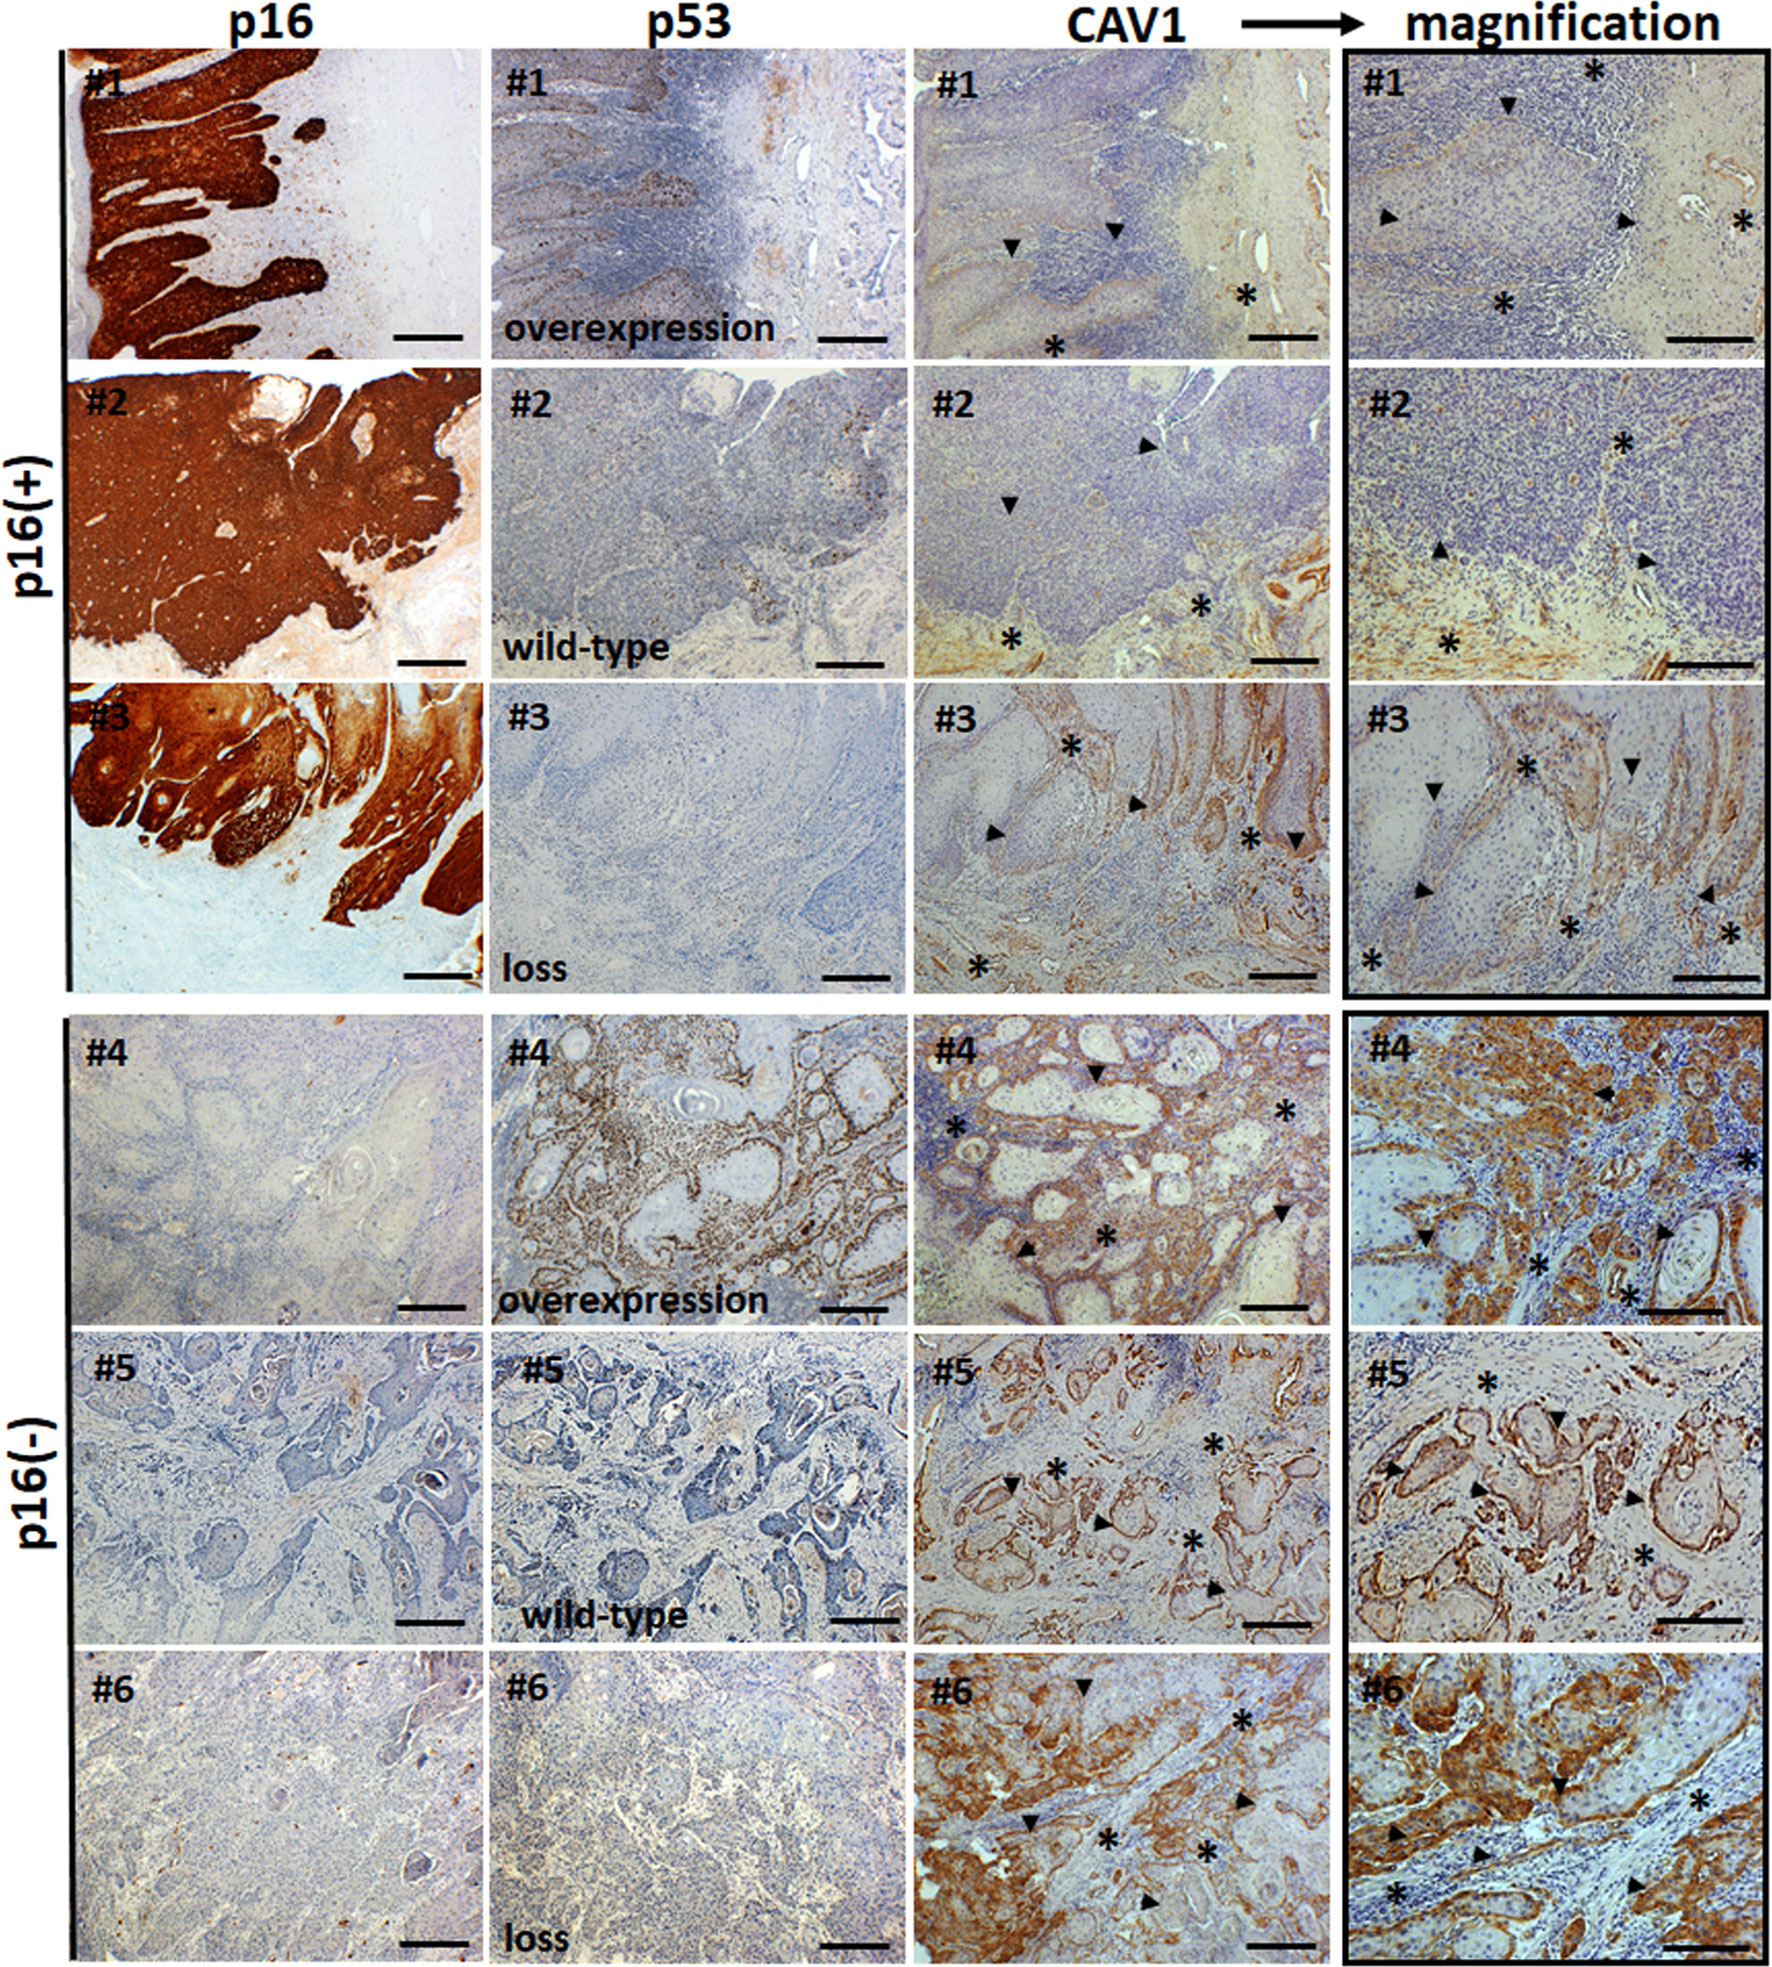

penile cancer photos download

Posts: penile cancer photos download